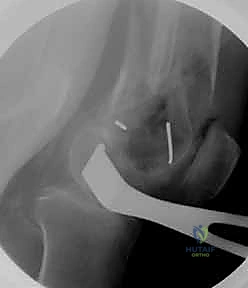

المرحلة الثالثة: إرجاع العظم (Reduction)

هذه هي الخطوة الأكثر أهمية. يقوم الدكتور هطيف بإعادة القطع العظمية المكسورة إلى مكانها التشريحي الأصلي. إذا كان الكسر ممتداً داخل المفصل، يتم تثبيت السطح المفصلي أولاً باستخدام مسامير دقيقة لضمان سطح أملس يمنع الاحتكاك والخشونة مستقبلاً.

- مناظير المفاصل بدقة 4K: في حال وجود إصابات مصاحبة في غضاريف أو أربطة الركبة (مثل الرباط الصليبي)، يتم علاجها بالمنظار في نفس وقت تثبيت الكسر.